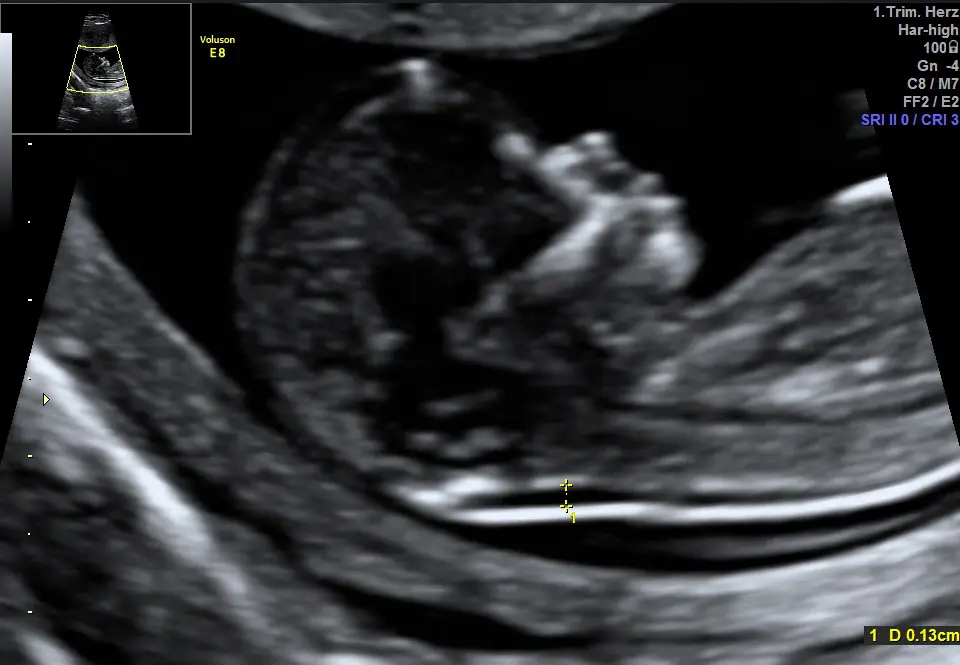

Die Nackenfaltenmessung ist eine Ultraschalluntersuchung, die im ersten Trimester der Schwangerschaft durchgeführt wird. Dabei wird die Dicke der Nackenfalte des Embryos gemessen. Eine dicke Nackenfalte kann ein Hinweis auf ein erhöhtes Risiko für bestimmte Chromosomenstörungen sein.

Wenn die Nackenfalte des Embryos zu dick ist, bedeutet dies nicht automatisch, dass das Kind eine Chromosomenstörung hat. Es bedeutet jedoch, dass das Risiko für eine Chromosomenstörung erhöht ist. In diesem Fall wird die Schwangere in der Regel zu weiteren Untersuchungen, wie z. B. Einer Fruchtwasseruntersuchung, geraten.